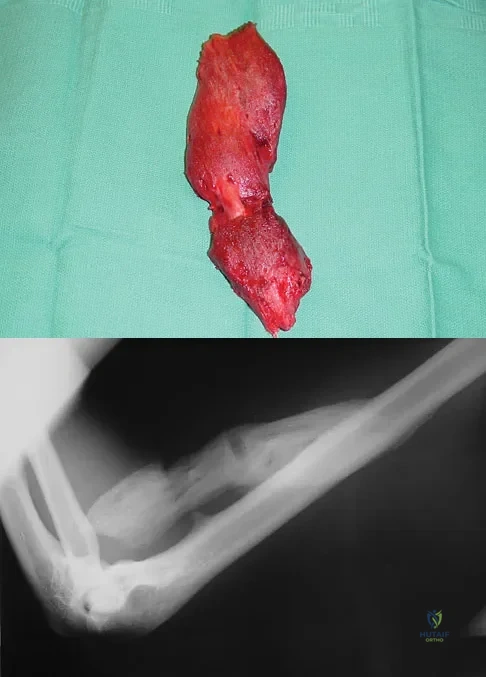

Figure 42 is a transverse MRI scan of the left shoulder. The arrow points to which of the following structures?

Explanation

The figure shows an axial image of the shoulder immediately inferior to the coracoid process. The subscapularis tendon, which can be traced from the myotendinous junction, is torn and detached from its lesser tuberosity attachment on the humerus. Lateral to the lesser tuberosity, the bicipital groove is empty. The arrow points to the subluxated biceps tendon. Superficial fibers of the subscapularis tendon are contiguous with the biceps retinaculum, which covers the bicipital groove and hold the biceps tendon in place. The vast majority of subscapularis tendon tears result in disruption of the biceps retinaculum with resultant subluxation of the tendon. Resnick D, Kang HS (eds): Internal Derangement of Joints: Emphasis on MR Imaging. Philadelphia, PA, WB Saunders, 1997, pp 308-317.

References:

- El-Khoury G: MRI of the Musculoskeletal System. Philadelphia, PA, JB Lippincott, 1998, p 234.